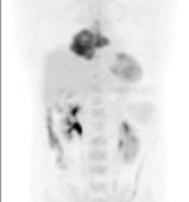

Scanner thorax abdomen pelvien : masse médiastinale antérieure et supérieure, absence d’atteinte du pédicule vasculaire, absence de nodule pulmonaire, scanner sous-diaphragmatique normal. Cible médiastinale taille 94 x 67 mm

TEP-FDG masse médiastinale hypermétabolique isolée